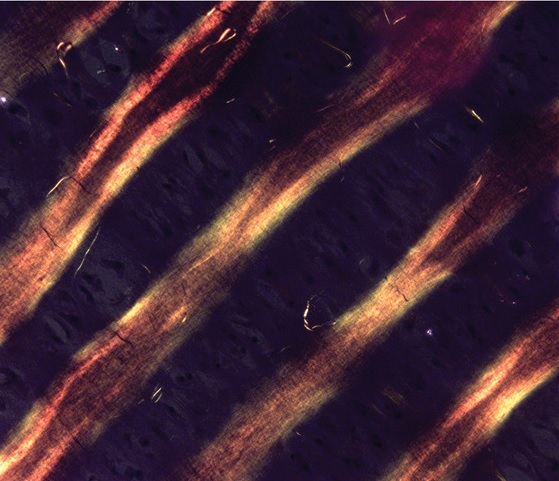

The ultimate objective of tissue engineering is to fabricate artificial living constructs with a structural organization and function that faithfully resembles their native tissue counterparts. For example, the deep zone of articular cartilage possesses a distinctive anisotropic architecture with chondrocytes organized in aligned arrays ≈1–2 cells wide, features that are oriented parallel to surrounding extracellular matrix fibers and orthogonal to the underlying subchondral bone. Although there are major advances in fabricating custom tissue architectures, it remains a significant technical challenge to precisely recreate such fine cellular features in vitro. Here, it is shown that ultrasound standing waves can be used to remotely organize living chondrocytes into high-resolution anisotropic arrays, distributed throughout the full volume of agarose hydrogels. It is demonstrated that this cytoarchitecture is maintained throughout a five-week course of in vitro tissue engineering, producing hyaline cartilage with cellular and extracellular matrix organization analogous to the deep zone of native articular cartilage. It is anticipated that this acoustic cell patterning method will provide unprecedented opportunities to interrogate in vitro the contribution of chondrocyte organization to the development of aligned extracellular matrix fibers, and ultimately, the design of new mechanically anisotropic tissue grafts for articular cartilage regeneration.